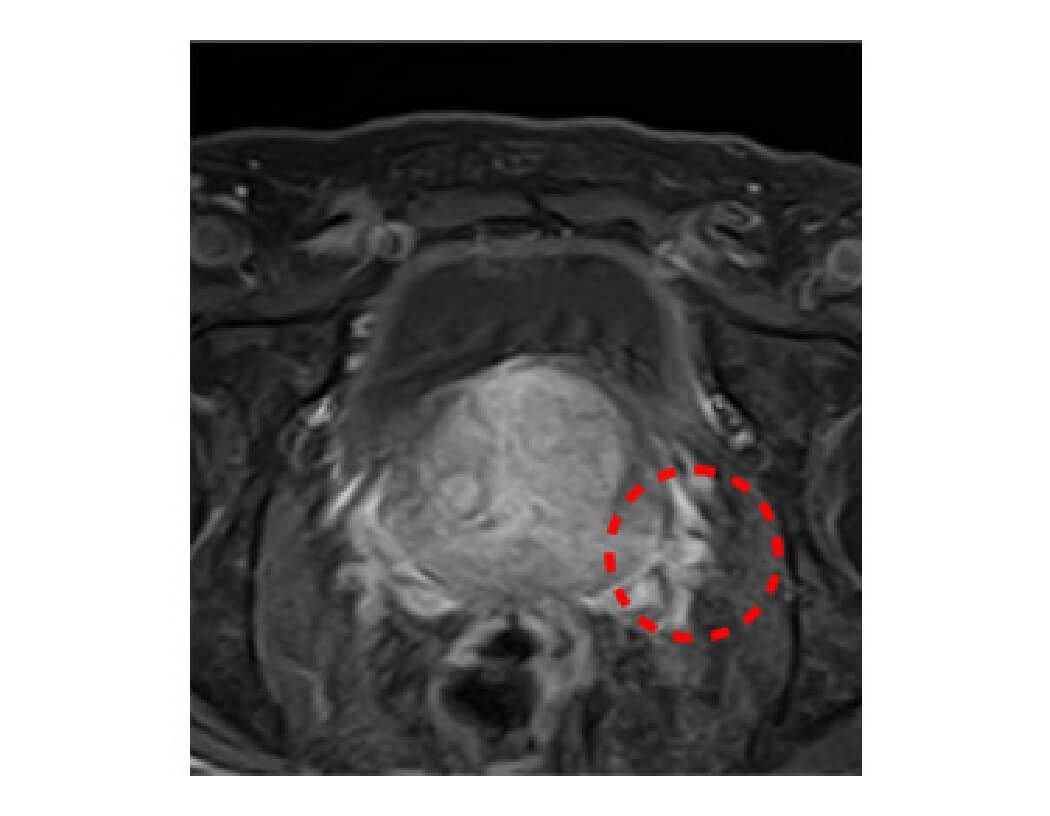

前立腺がんの症例